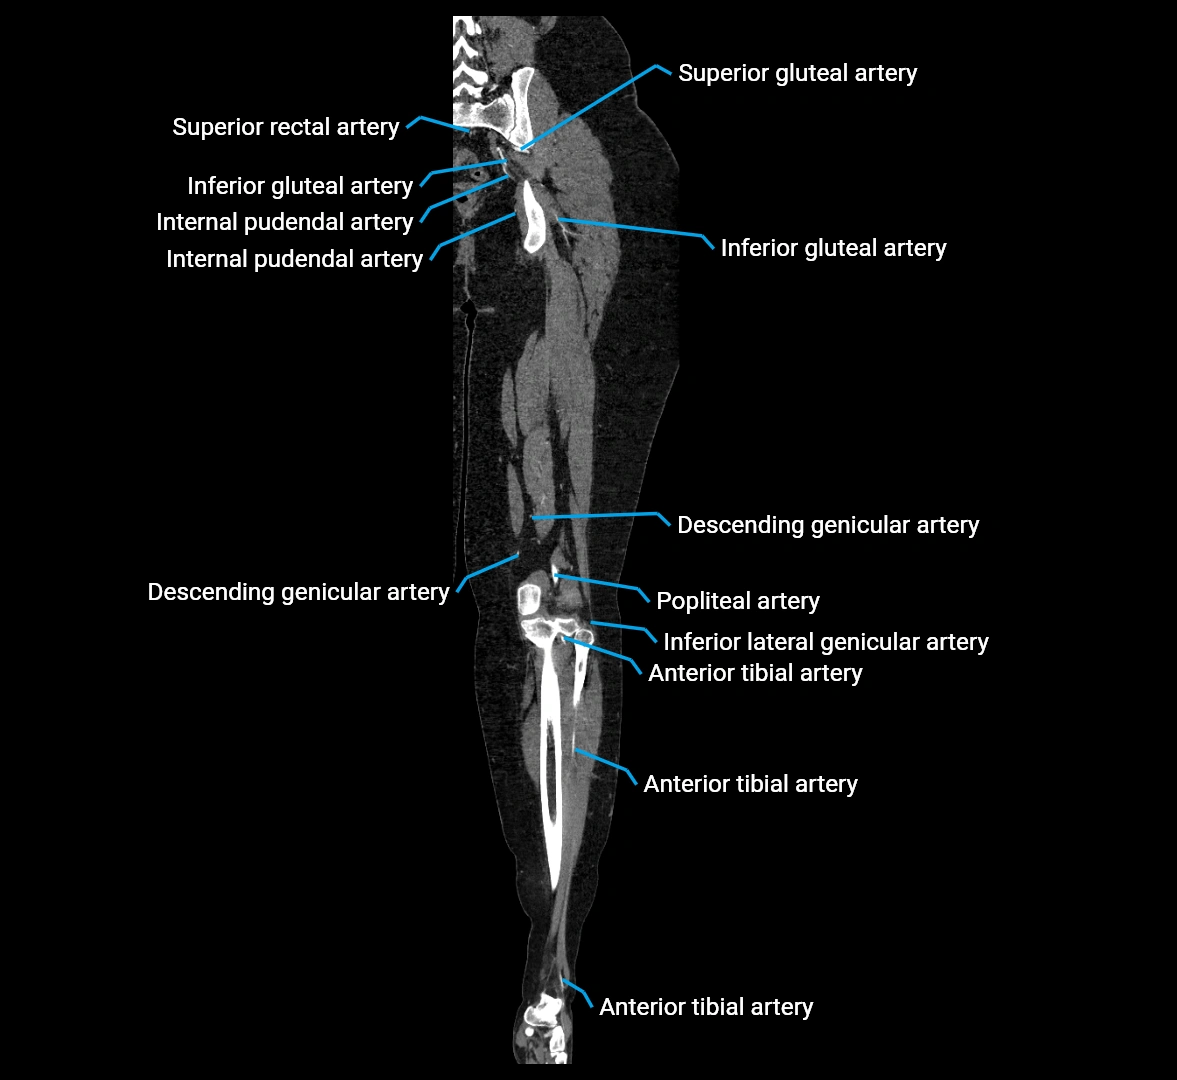

CT images

image

Contrast-enhanced CT (CTA):

• Gold standard for abdominal aortic imaging

• Provides excellent detail of lumen, wall, aneurysm, thrombus, and branch vessels

• Multiplanar and 3D reconstructions help in aneurysm measurement, stent graft planning, and dissection evaluation